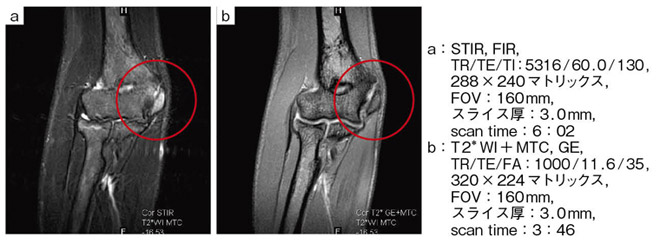

【RAPID KNEEコイルによる肘関節内側骨端障害例】